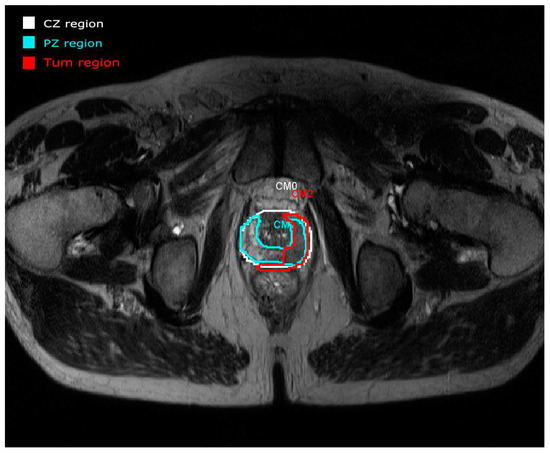

The PZ represents up to 70% of a normal prostate gland and around 75% of prostate cancers originate in this zone. The CZ represents about 25% of a normal healthy prostate gland in young adults. Even though the frequency of cancers originating here is much lower, they tend to be of the more aggressive type [14]. An example of a real study case provided by the panel visualization of the prostate tool [11] is depicted in Figure 2. All the overlays are annotated with manual drawings made by radiologists. Each region is represented by different colors (CZ in white and PZ in blue) focusing on a tumor area represented in red (Tum). This example shows the importance of making annotations in regions of interest. In this case, a manual segmentation is validated by experts.

Figure 2. An example of the anatomy (T2WI) panel visualization of the tool developed in [11] with the ROIs annotated by radiologists.